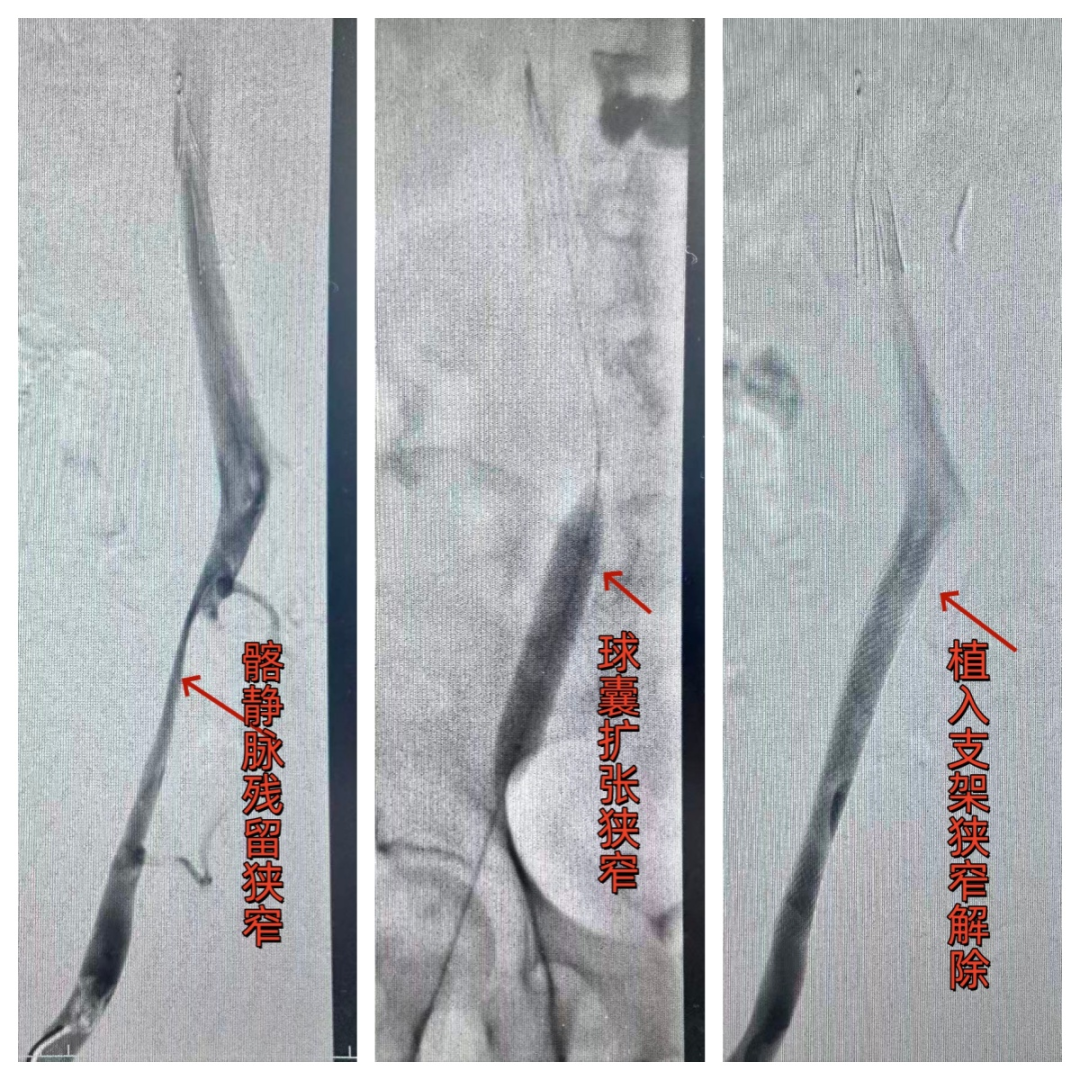

标准化诊疗流程:先通过3D静脉造影、超声定位血栓位置与血管解剖变异,明确潜在病因;再采用机械碎栓抽吸系统快速清除大部分血栓,配合导管定向溶栓溶解残余血栓,将溶栓周期从7天左右大幅缩短至24~48小时;针对髂静脉压迫、狭窄,同步实施球囊扩张与支架植入,从根源降低复发风险;高风险患者同期置入下腔静脉滤器,拦截脱落血栓、杜绝肺栓塞,后续可适时取出,实现全程安全防护。